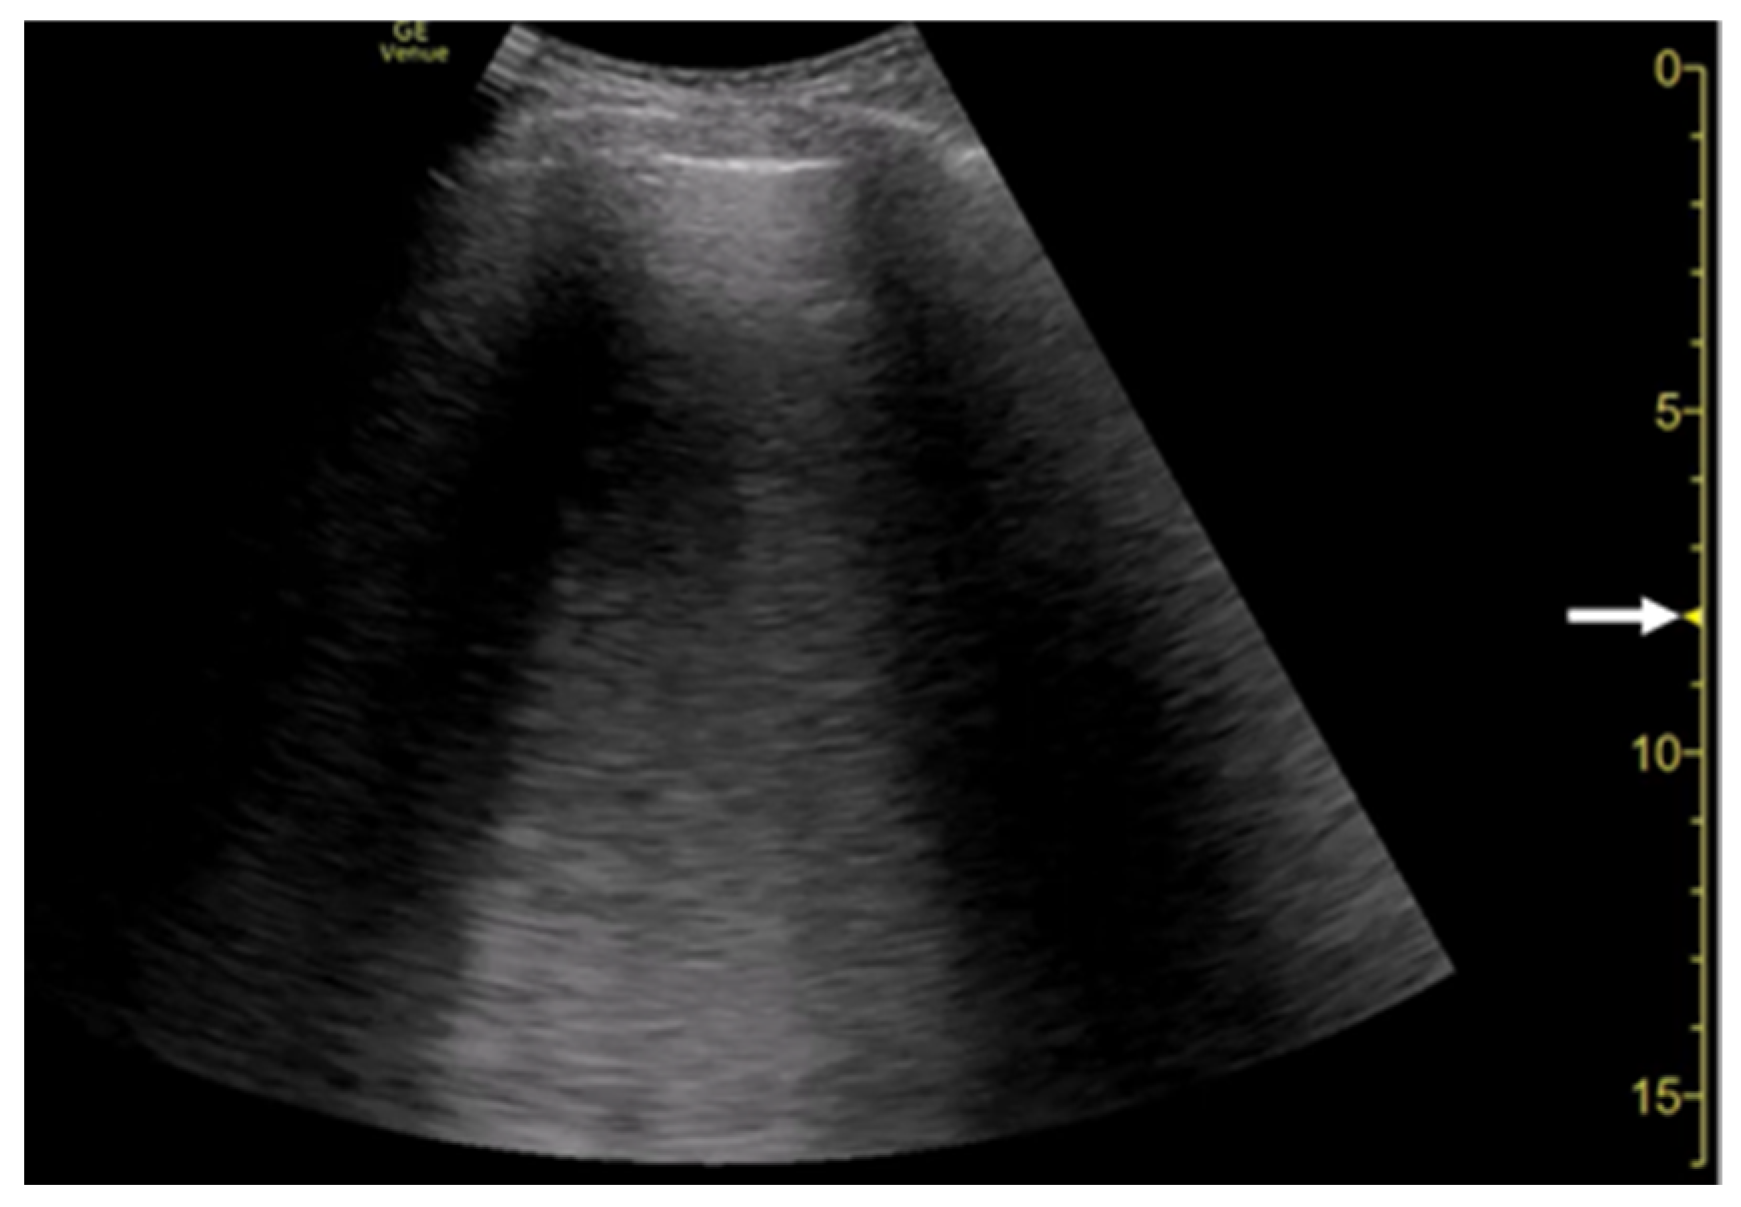

2. Generation of Vertical Artifacts

2.2. The Theory of Acoustic Trap

2.3. Our Basic Research Supporting the Theory